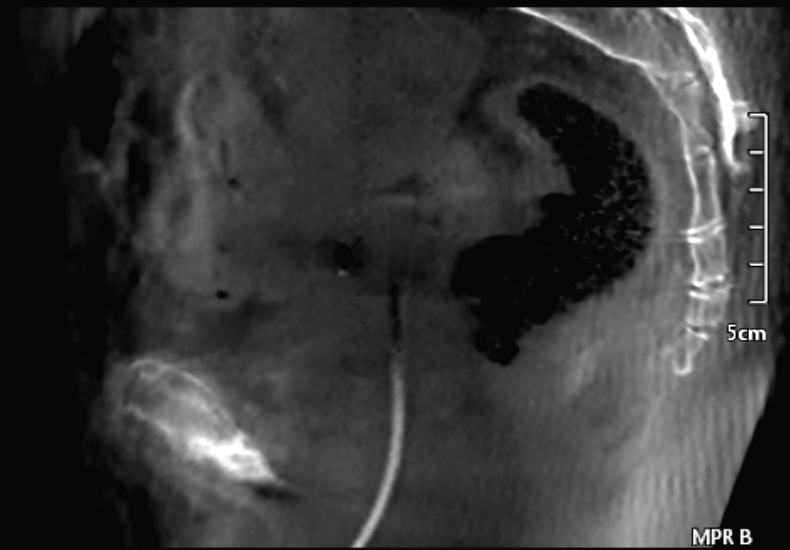

Just curious if anyone has Canon Alphenix systems with CBCT options. Our new system has this subtle central ring artifact, even after detector replacement. It appears stronger with a uniform ACR phantom, but is also visible from clinical cases, especially from sagittal or coronal views.

[cid:4daacfa6-171f-496c-9767-579795ce81d2]